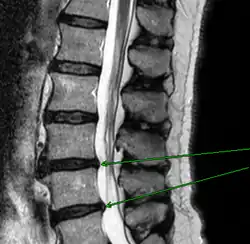

![]() Положение поясничных позвонков человека (отмечены красным). Пять позвонков обозначаются (сверху вниз) L1, L2, L3, L4 и L5. | |

Механическое смещение одного из поясничных позвонков, переохлаждение, локальная инфекция, опухоли, деградация тканей, могут привести к воспалительному процессу в позвоночно-двигательном сегменте, последующим мучительным болям, вынужденным положениям тела. Очень распространённой причиной патологии в поясничном отделе позвоночника является неверное распределение нагрузки на поясничный отдел позвоночника, когда дополнительный вес (а иногда и собственный вес) поднимаются с единственным рычагом в поясничном отделе позвоночника. Частым заболеванием в поясничном отделе позвоночника являются грыжи межпозвоночных дисков — выпячивания пульпозного ядра диска за пределы его фиброзного кольца. В 48 % случаев межпозвоночные грыжи локализуются на уровне L5-S1 пояснично-крестцового отдела, в 46 % случаев — на уровне L4-L5, и лишь в оставшихся 6 % случаев — между другими позвонками поясничного, шейного или грудного отделов позвоночника.